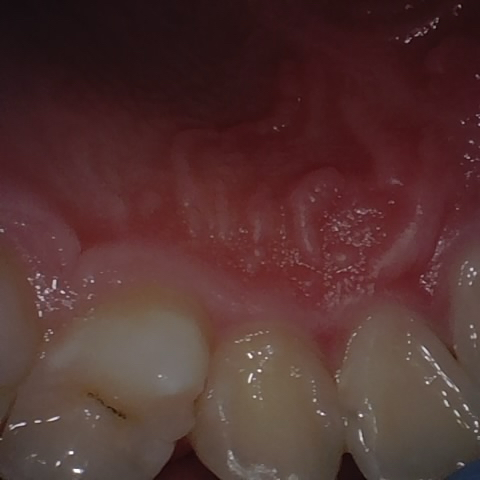

Annotated as "Good"